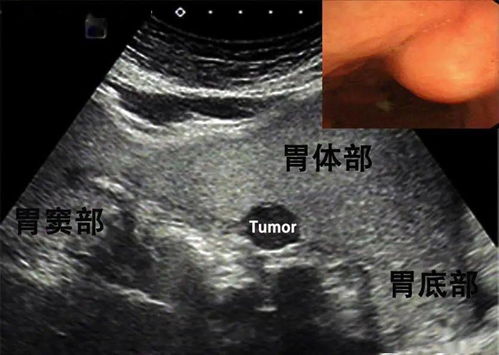

不同的癌症类型有其独特的特性。如肺癌,早期症状隐匿,一旦发生转移,恶化迅速,特别是淋巴结或远处转移,多属晚期。肝癌的复发率高,且晚期才发现的患者预后通常较差。而乳腺癌经过规范治疗后,仍有长期复发的可能,需长期监测。